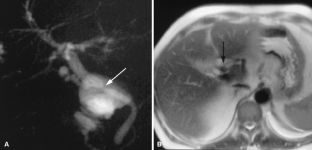

Usual and unusual causes of extrahepatic cholestasis: assessment with magnetic resonance cholangiography and fast MRI

Cholestasis may result from hepatocellular (intrahepatic) disease or biliary tract (extrahepatic) abnormalities. Etiologies causing extrahepatic cholestasis are extremely diverse and invasive procedures, such as endoscopic retrograde cholangiopancreatography (ERCP) and percutaneous transhepatic cholangiography (PTC), were previously required to establish the diagnosis. Due to refinements of magnetic resonance imaging (MRI) techniques, the patient with extrahepatic cholestasis currently can be evaluated noninvasively, and the information revealed frequently exceeds the findings obtained by ERCP and PTC. In this essay, we illustrate the classic MR cholangiographic (MRC) and MRI features of a variety of disorders causing extrahepatic cholestasis, including non-neoplastic disorders of the biliary tract (congenital abnormalities, infectious processes, iatrogenic disorders, and postsurgical complications) and neoplastic conditions (e.g., tumors of the pancreas, biliary tree, liver, ampulla, and regional lymph nodes). In most cases, familiarity with the key MRC features in addition to information obtained via cross-sectional MR images provide sufficient information for adequate lesion characterization.